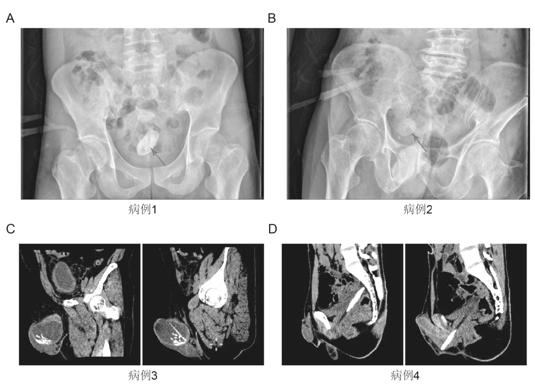

ABCD分别为塑料管、树枝、牙签、筷子丨参考文献1

[1]李世豪, 刘宏伟, 朱奕, et al. 性自慰导致膀胱尿道异物4例分析 / Analysis of 4 cases of foreign bodies in bladder and urethra caused by masturbation. 中国性科学 / Chinese Journal of Human Sexuality. 2023;32(7):1-4. doi:10.3969/j.issn.1672-